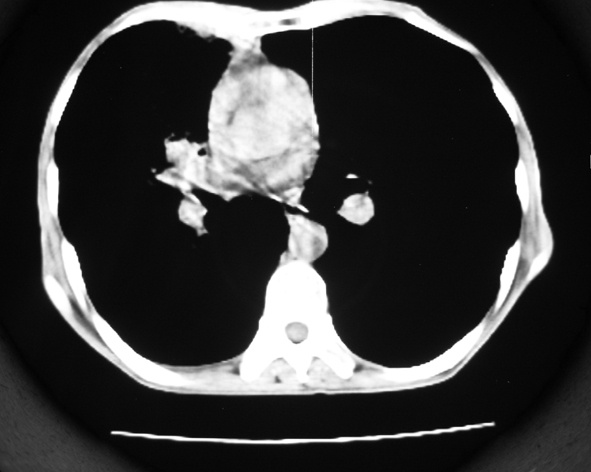

男53岁,咳嗽气短,以往身体健康.

右肺上叶多发多形态空洞及增殖灶,可见团块钙化,胸膜肥厚、粘连,考虑继发型肺结核可能性大

1.右肺上叶干酪性肺炎,2。肺气肿,肺大泡

右肺上中叶结核干酪性肺炎

右肺中上叶干酪性肺炎。

支持右上肺继发性肺结核并干酪性肺炎,右肺大泡,左肺代偿性气肿。